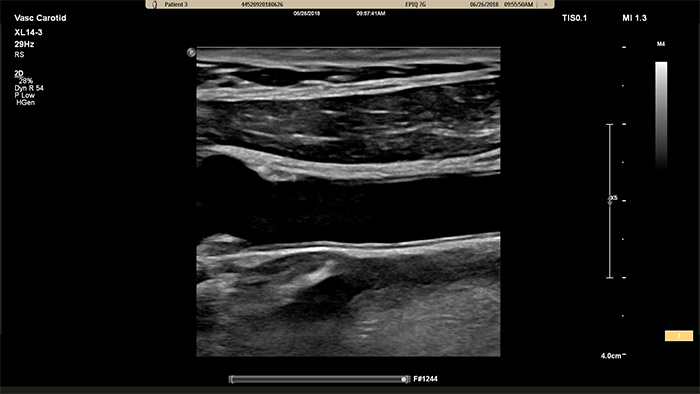

Il trasduttore XL14-3 xMATRIX incorpora un numero incredibile di elementi, addirittura 56.000, tutti collegati a un microcanale separato. Il trasduttore XL14-3 è dotato di messa a fuoco elettronica multidimensionale per immagini a spessore ultrasottile dell'anatomia vascolare e della morfologia della placca. Vantaggio principale: eccezionale affidabilità diagnostica nella valutazione della stenosi e della placca vulnerabile.